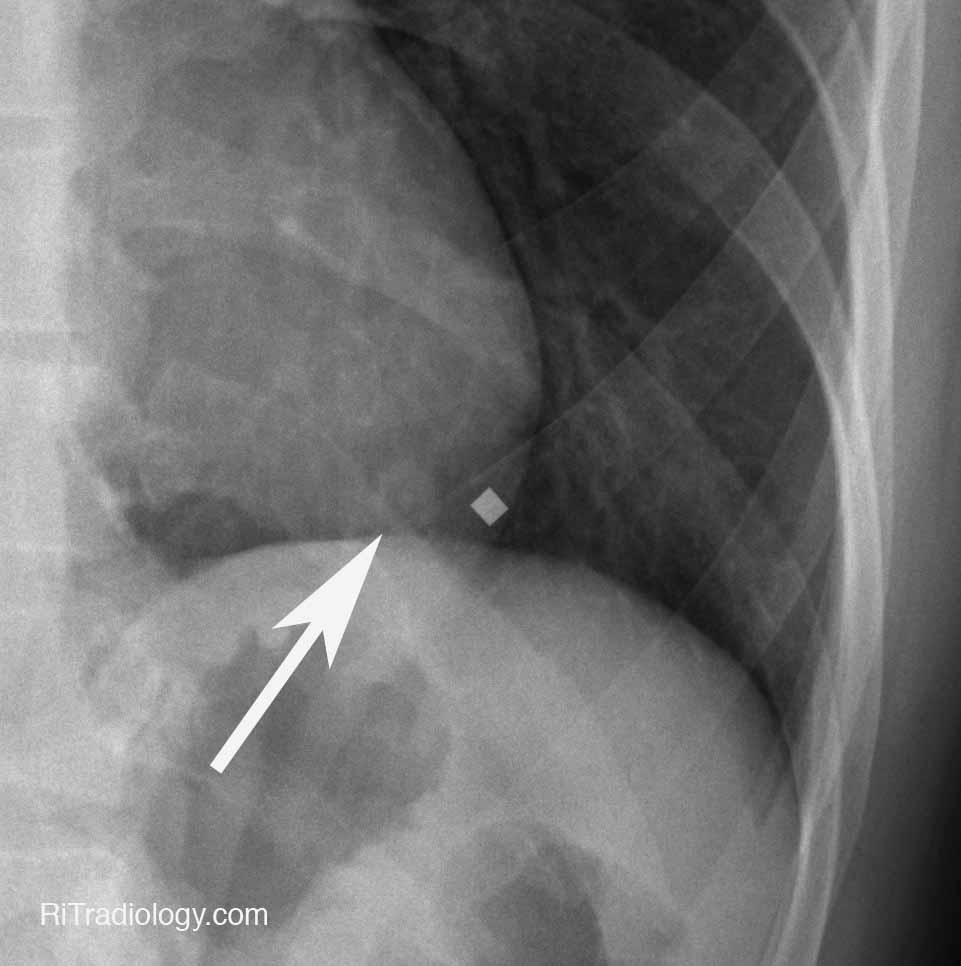

Chest X Ray With Nipple Markers Cpt Code . Navigate coding with ease in our comprehensive guide. Nipple markers can be a useful technique in the evaluation of small radiodensities overlying the expected position of the nipple on a. Nipple shadows are apparent on approximate 10% of ap/pa views of the chest. The following is provided as a quick reference guide only and not inclusive of all diagnostic imaging codes. 2024 cpt code quick reference guide. Metallic bbs that are placed on the nipples to help the radiologist distinguish a nipple shadow from a lung mass. Unlock the specifics of chest x ray cpt code for billing and insurance purposes. Any coding inquiry not listed. *these cpt codes represent the most commonly ordered mri exams. When present, they need to be differentiated from more significant intra thoracic pleural or pulmonary nodules. Nipple shadows can be seen in patients with different genders and age.

RiT radiology December 2011 Chest X Ray With Nipple Markers Cpt Code Nipple markers can be a useful technique in the evaluation of small radiodensities overlying the expected position of the nipple on a. The following is provided as a quick reference guide only and not inclusive of all diagnostic imaging codes. Nipple shadows can be seen in patients with different genders and age. Metallic bbs that are placed on the nipples. Chest X Ray With Nipple Markers Cpt Code.